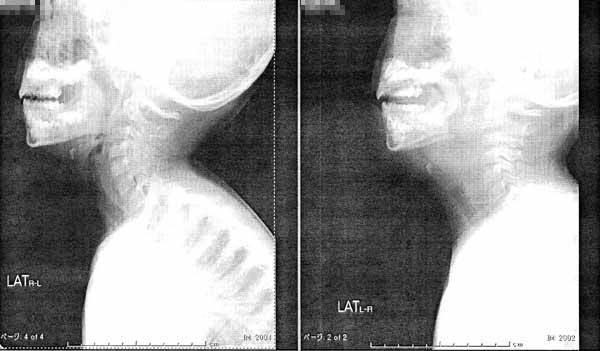

○胸正面

入院時の白いもやが肺炎。今日はもうなくなっている。

ちなみに入院時の写真の気道には挿管のチューブが見える。

今日 入院時

○気管支正面像

入院時、気道が極端に細くなっているのがよくわかる。

呼吸は吸う時も吐く時も「いびき」のような音が鳴り、苦しそうだった。